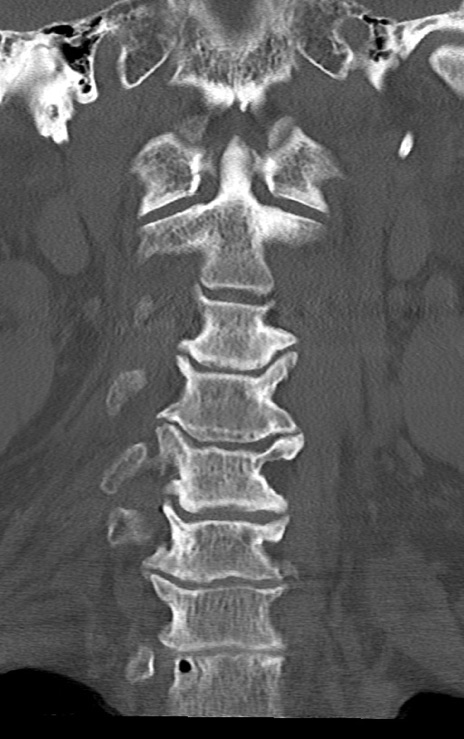

頚椎CT

矢状断像